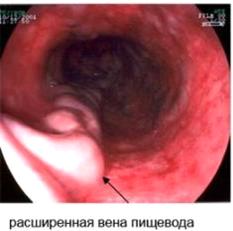

Варикозное расширение вен пищевода вследствие портальной гипертензии классифицируется по степеням (А.Г. Шерцингер):степени - расширение до 2-3 мм - вероятность возникновения кровотечения 25-9%.степени - расширение до 3-4 мм - возникновения кровотечения 42-15%..степени - расширение более 5 мм возникновения кровотечения 87-54%.

—  Портограмма (PV - воротная вена, SV - селезеночная вена, SM - верхняя брыжеечная вена, IM - нижняя брыжеечная вена, RG - правая вена желудка, GC - коронарная вена желудка, V - варикоз вен кардии и пищевода)